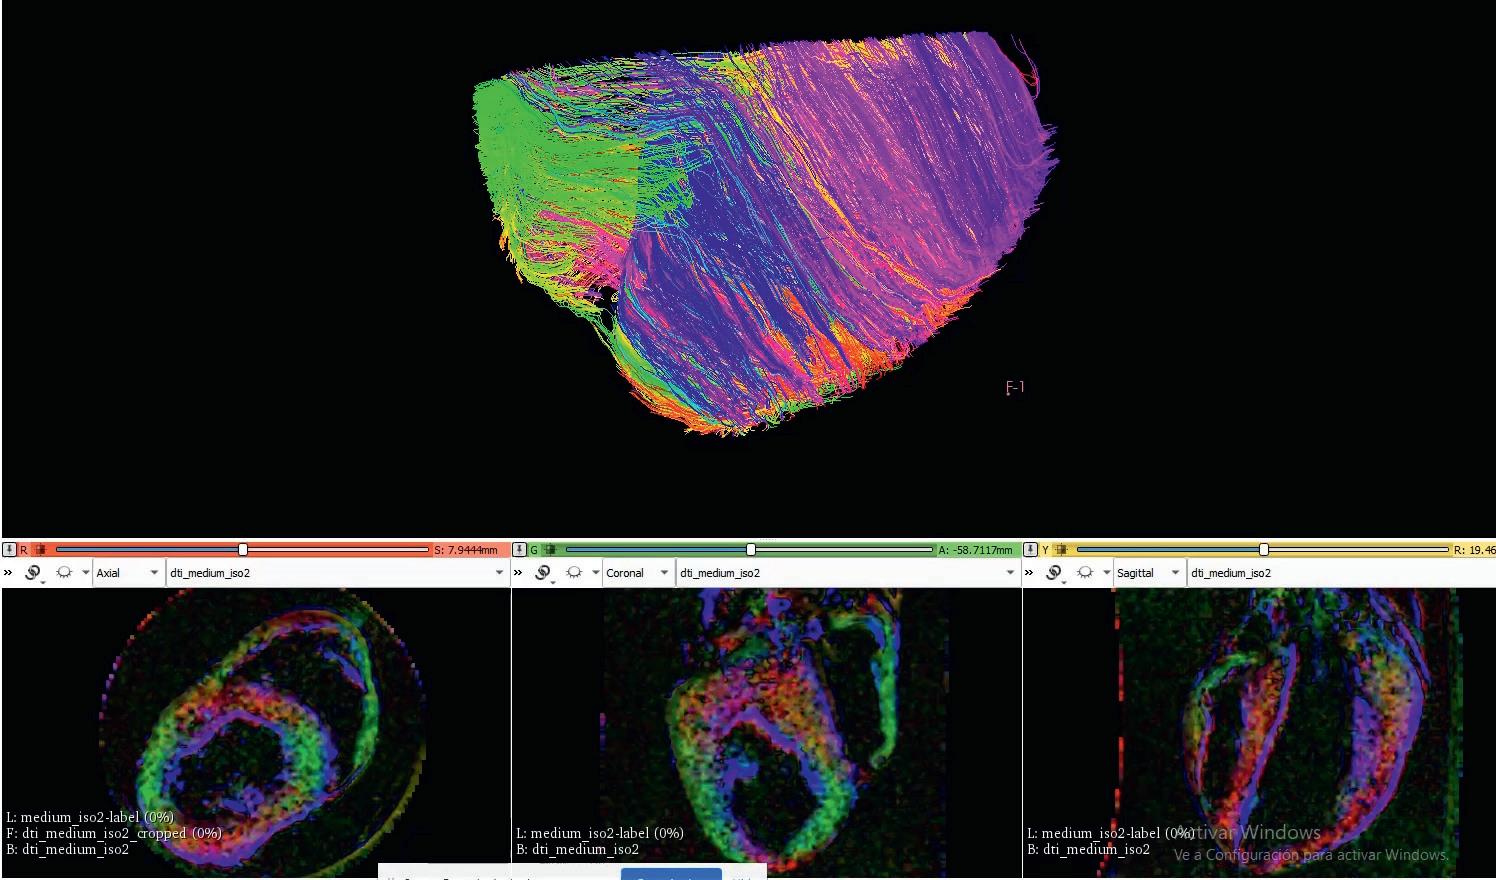

throughout its thickness. This is how the heart has evolved over millions of years in order to pump blood as efficiently as possible,” he outlines. Researchers are using magnetic resonance imaging (MRI) on pigs’ hearts to determine this structure to a high degree of precision, which can then provide a solid basis for designing and producing

“The orientation of the different layers of tissue in the heart changes slightly

the BioVAD. “We can then use 3-D printing, and other materials and technologies, to structure stem cells in such a way that they can produce this tissue in a way that mimics the structure we see from the MRI images,” says Dr Mazo Vega.

are oriented in the ideal way, which Dr Mazo Vega says is crucial to the effectiveness of the BioVAD in helping to restore cardiac function. “We can develop cardiomyocytes in the lab, muscles which contract. But if you have one cell contracting in one direction, and others contracting in different directions, then the sum of all these forces is going to be very minor,” he points out. The orientation of cardiac layers varies across the thickness of the heart, which is what researchers in the project are seeking to replicate. “With our 3D printing technology we can build scaffolds with very different geometries. This geometry is then going to affect the functionality of the tissue that we build,” continues Dr Mazo Vega. “We can build very, very thin fibres that can help cells to align themselves in certain orientations.”

The orientation of the different layers of tissue in the heart changes slightly throughout its thickness. This is how the heart has evolved over millions of years in order to pump blood as efficiently as possible.

Reconstruction of cardiac fibre alignment in a porcine heart, showing how the orientation of cardiomyocytes varies. Different colours depict different orientations.

Reconstruction of cardiac fibre alignment in a porcine heart, showing how the orientation of cardiomyocytes varies. Different colours depict different orientations.